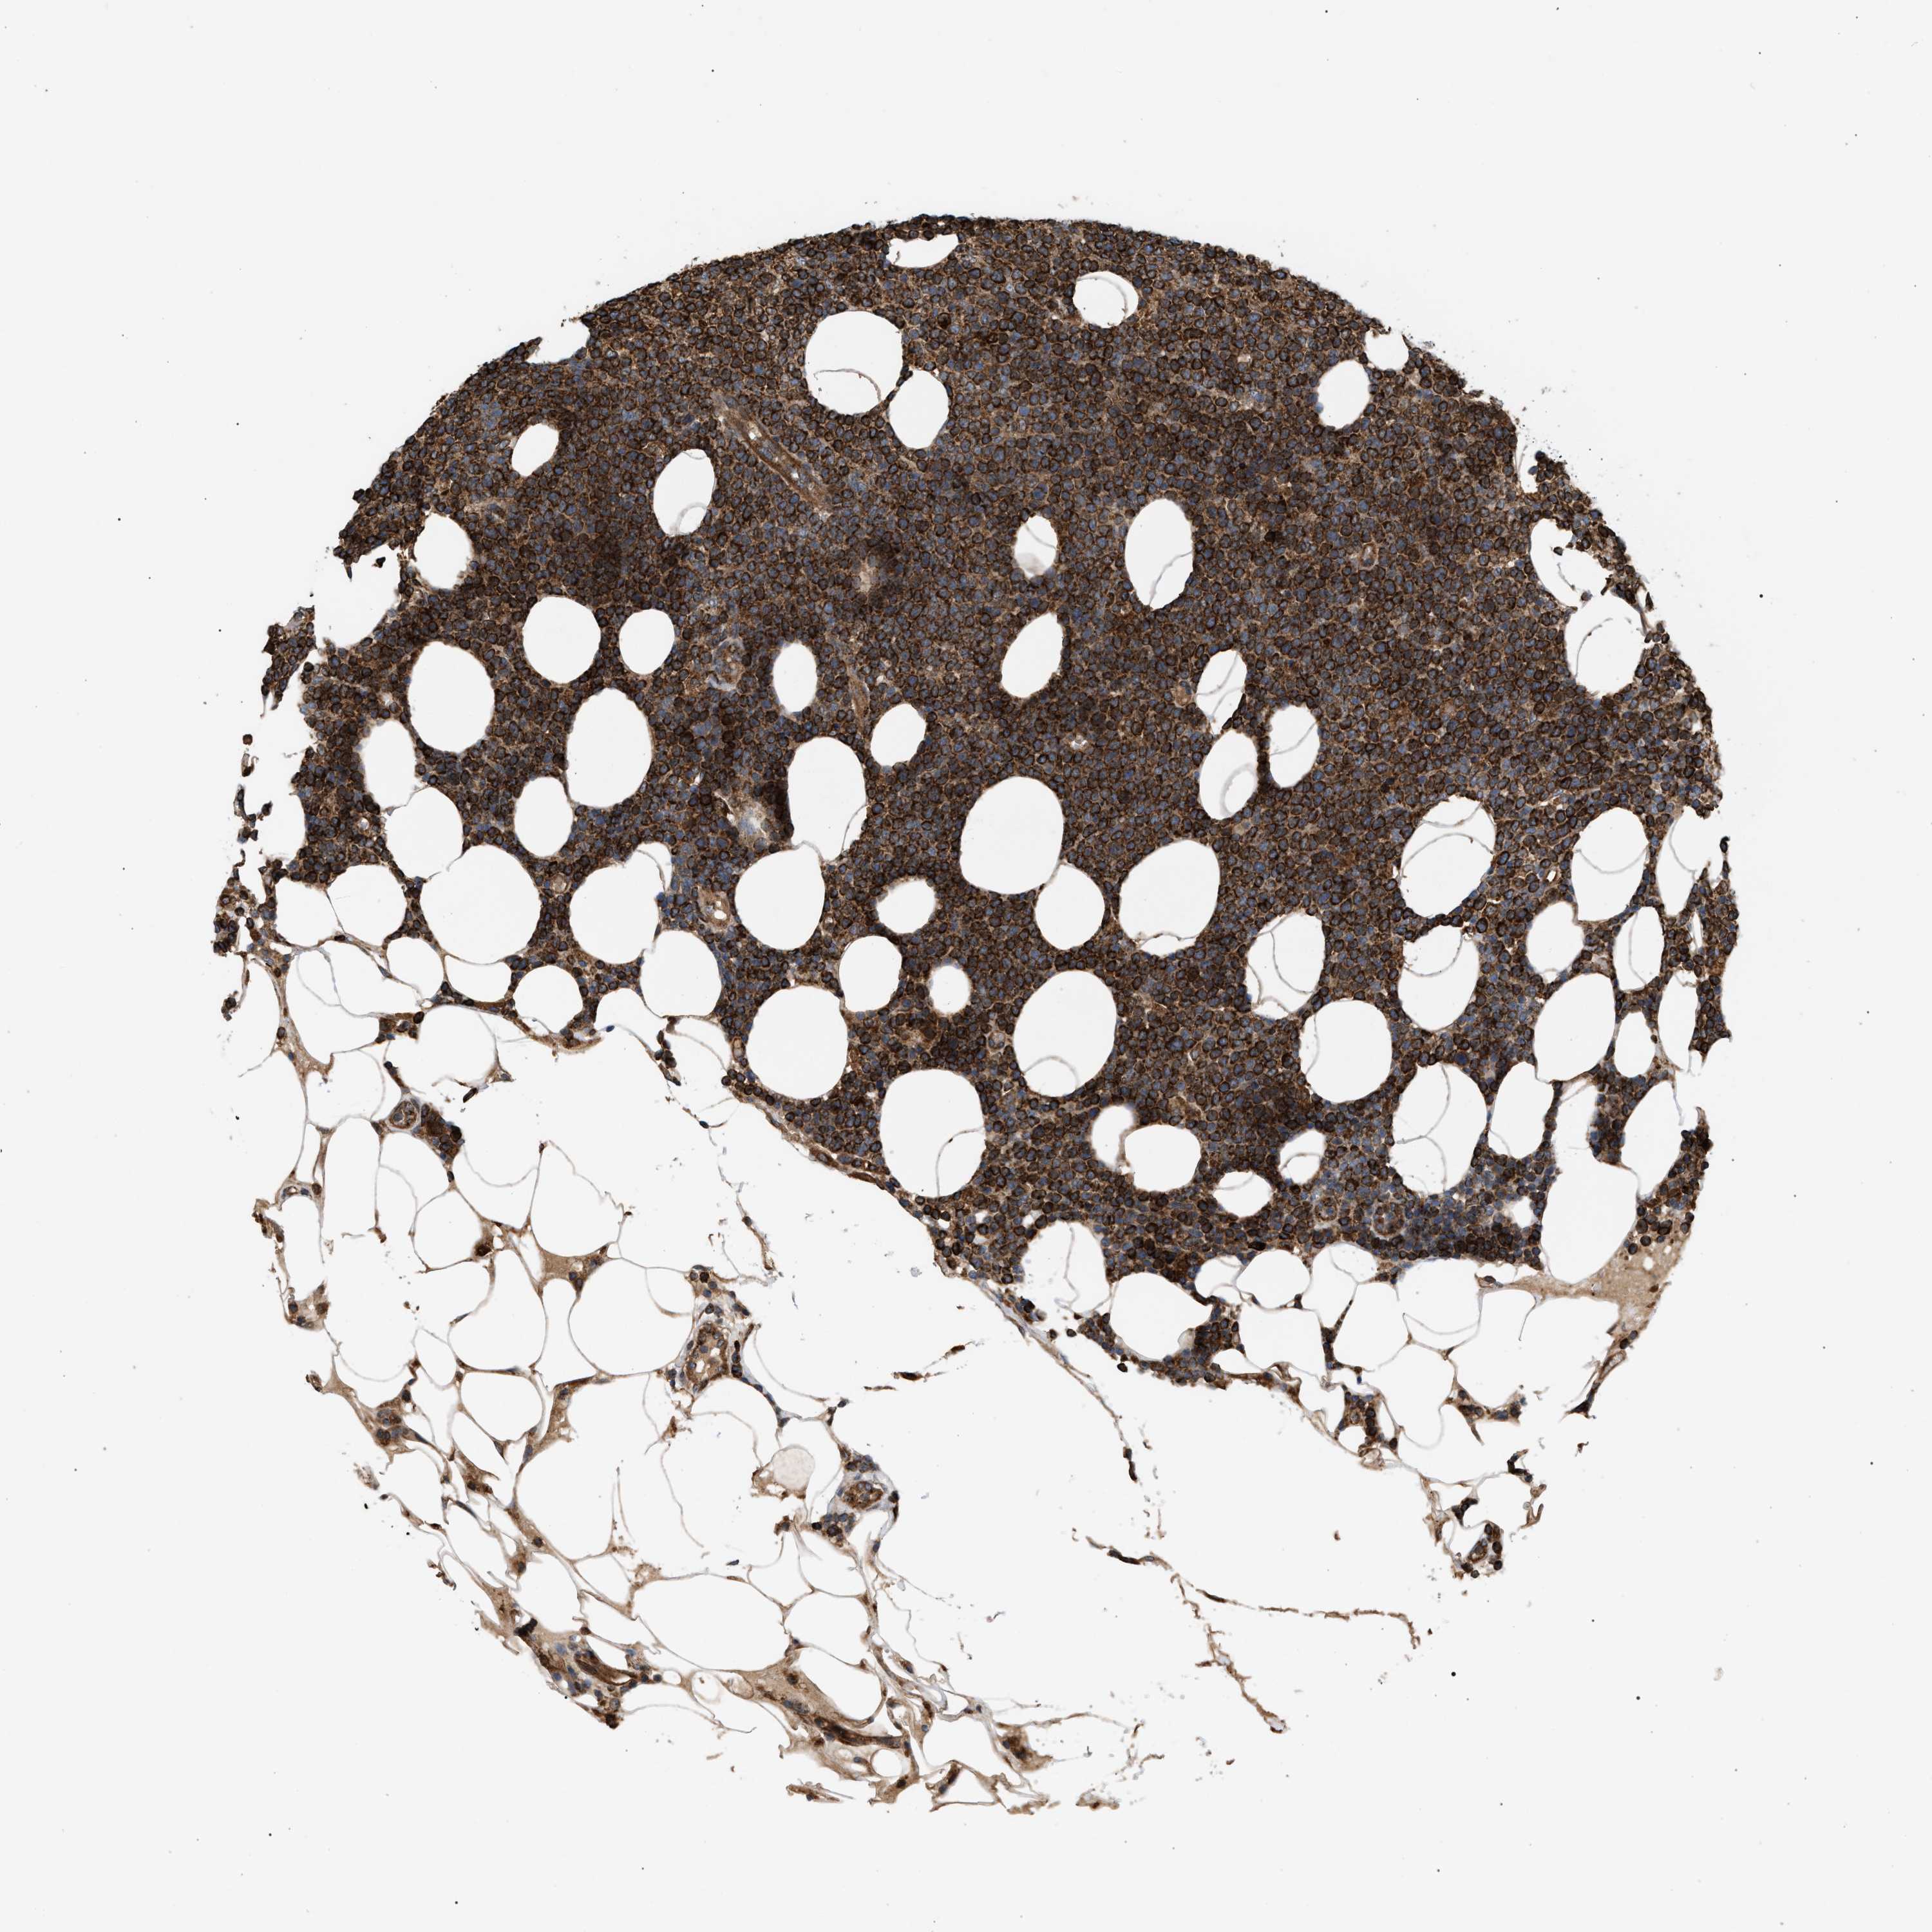

CANCER LYMPHOMA Show tissue menu

LYMPHOMA - Protein expressioni

A mouse-over function shows sample information and annotation data. Click on an image to view it in a full screen mode. Samples can be filtered based on level of antibody staining by selecting one or several of the following categories: high, medium, low and not detected. The assay and annotation is described here.

Each image is clickable and will lead to virtual microscopy that enables deeper exploration of all samples and also displays staining intensity scores, fraction scores and subcellular localization as well as patient and tissue information for each sample.

Antibody HPA019369

Antibody HPA021323

Staining

High

Medium

Low

Not detected

Intensity

Strong

Moderate

Weak

Negative

Quantity

>75%

75%-25%

<25%

None

Location

Nuclear

Cytoplasmic/membranous

Cytoplasmic/membranous,nuclear

Hodgkin's disease, NOS

Malignant lymphoma, non-Hodgkin's type, High grade

Malignant lymphoma, non-Hodgkin's type, Low grade